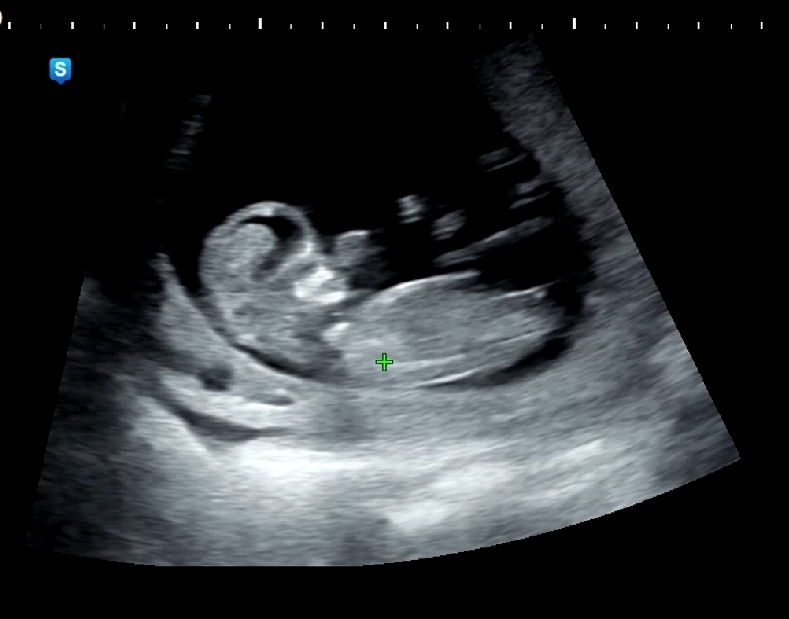

11주4일차 각도법 봐주세요~~~

11주4일차 아가를 만나고 왔는데 아직 성별을 몰라 고수님들 각도법 좀 부탁드립니다~~~